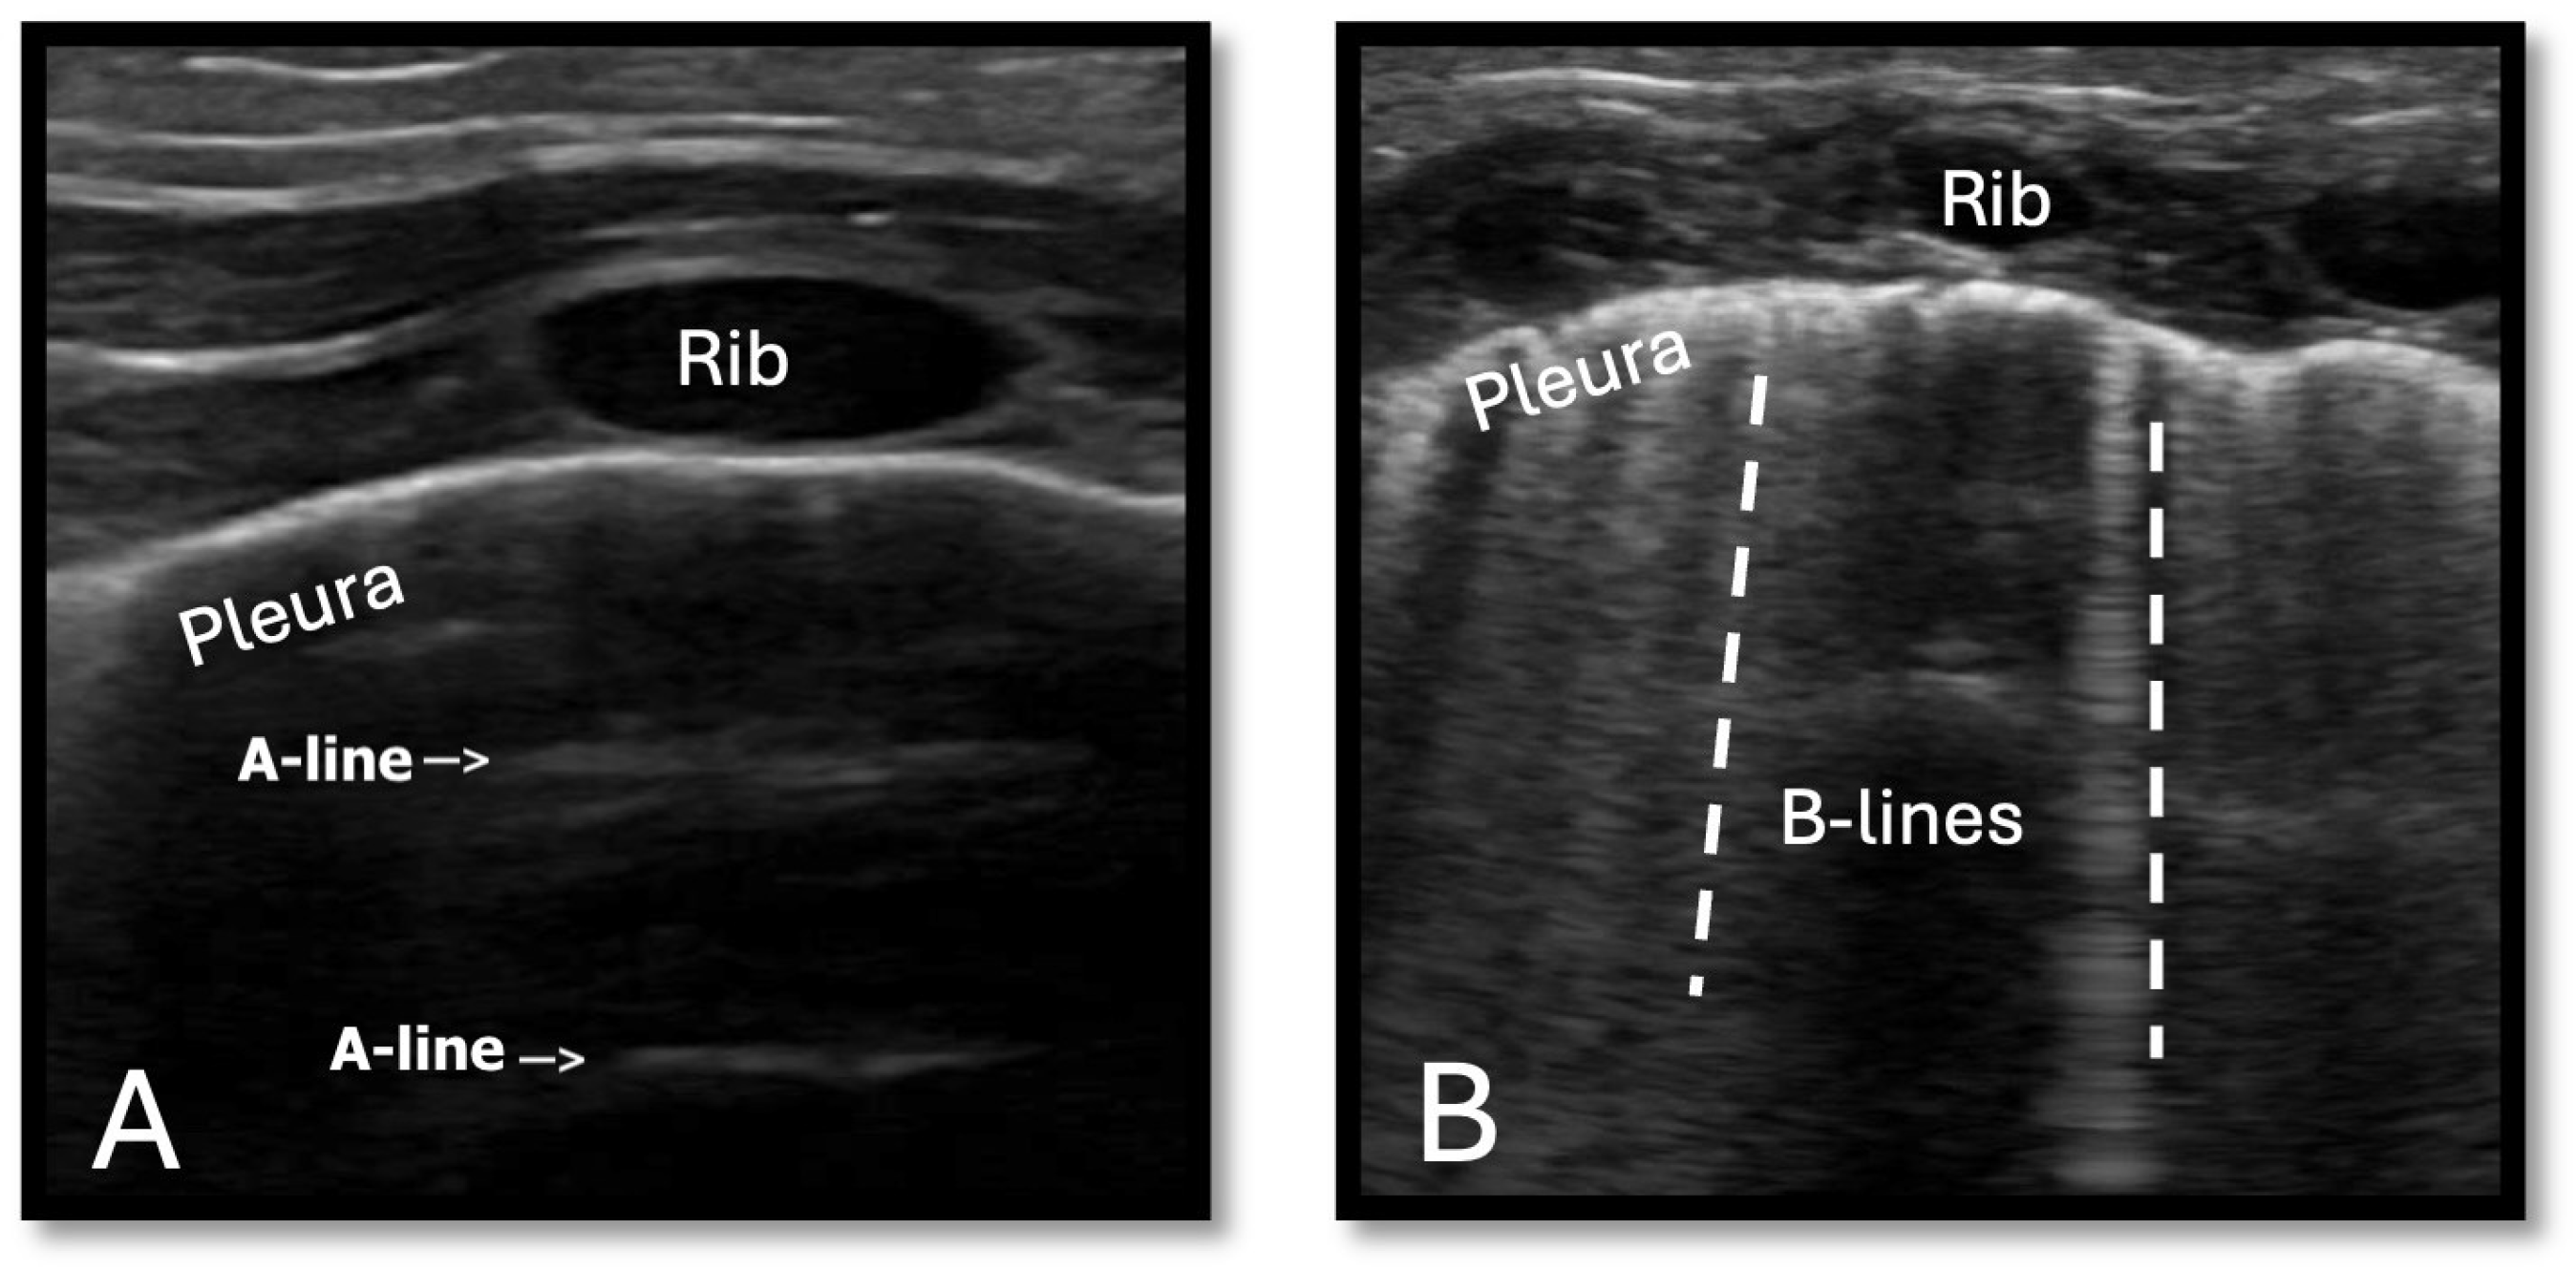

3.2. Monitoring Pulmonary Overcirculation

- Zong, H.F.; Guo, G.; Liu, J.; Bao, L.L.; Yang, C.Z. Using lung ultrasound to evaluate pulmonary water content. Pediatr. Pulmonol. 2020, 55, 729–739. [Google Scholar] [CrossRef]

- Kaya, B.; Dilli, D.; Sarikaya, Y.; Akduman, H.; Citli, R.; Orun, U.A.; Tasar, M.; Zenciroglu, A. Lung ultrasound in the evaluation of pulmonary edema in newborns with critical congenital heart disease. Pediatr Neonatol. 2024, 65, 532–538. [Google Scholar] [CrossRef]